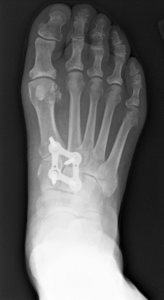

Foot and ankle procedures including bunion repair, foot reconstructions